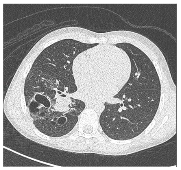

Figure 2. Congenital pulmonary malformations with large and small cystic areas of hyperinflation. No systemic irrigation was observed.

In the postnatal period, the gold standard remains contrast-enhanced computed tomography (CT angiography), which enables high-resolution evaluation of the bronchial tree integrity, characterization of parenchymal architecture (Figure 4), and assessment of the number and size of cysts (Figure 2). It also allows for precise visualization of aberrant systemic vessels (Figure 5), as well as evaluating compressive effects on mediastinal structures.